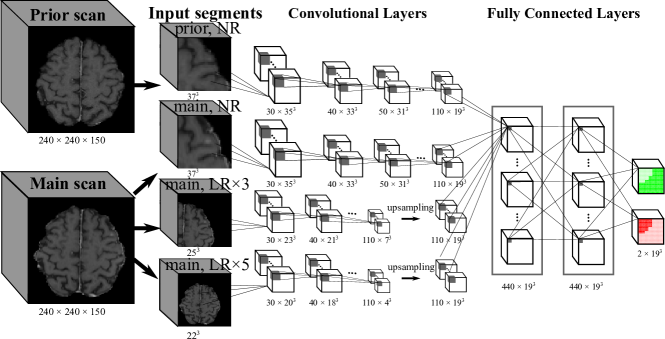

Refer to caption

Figure 3: The modified DeepMedic architecture, called DeepMedic+ in this work, uses one additional path for temporal prior volumes. The normal resolution (NR) subvolumes from both the prior and main datasets as well as two low resolution (LR) subvolumes from the main dataset are input segments of different network paths. The neurons of the last layers have receptive fields of 193superscript19319^{3} voxels. The final two output channels sum to 1. The feature map dimensions during training in our work are displayed as Number ×\times Size. Note that the feature dimensions are only for training. For inference, a different input size can be used, since DeepMedic is a fully convolutional network. Modified from 22.